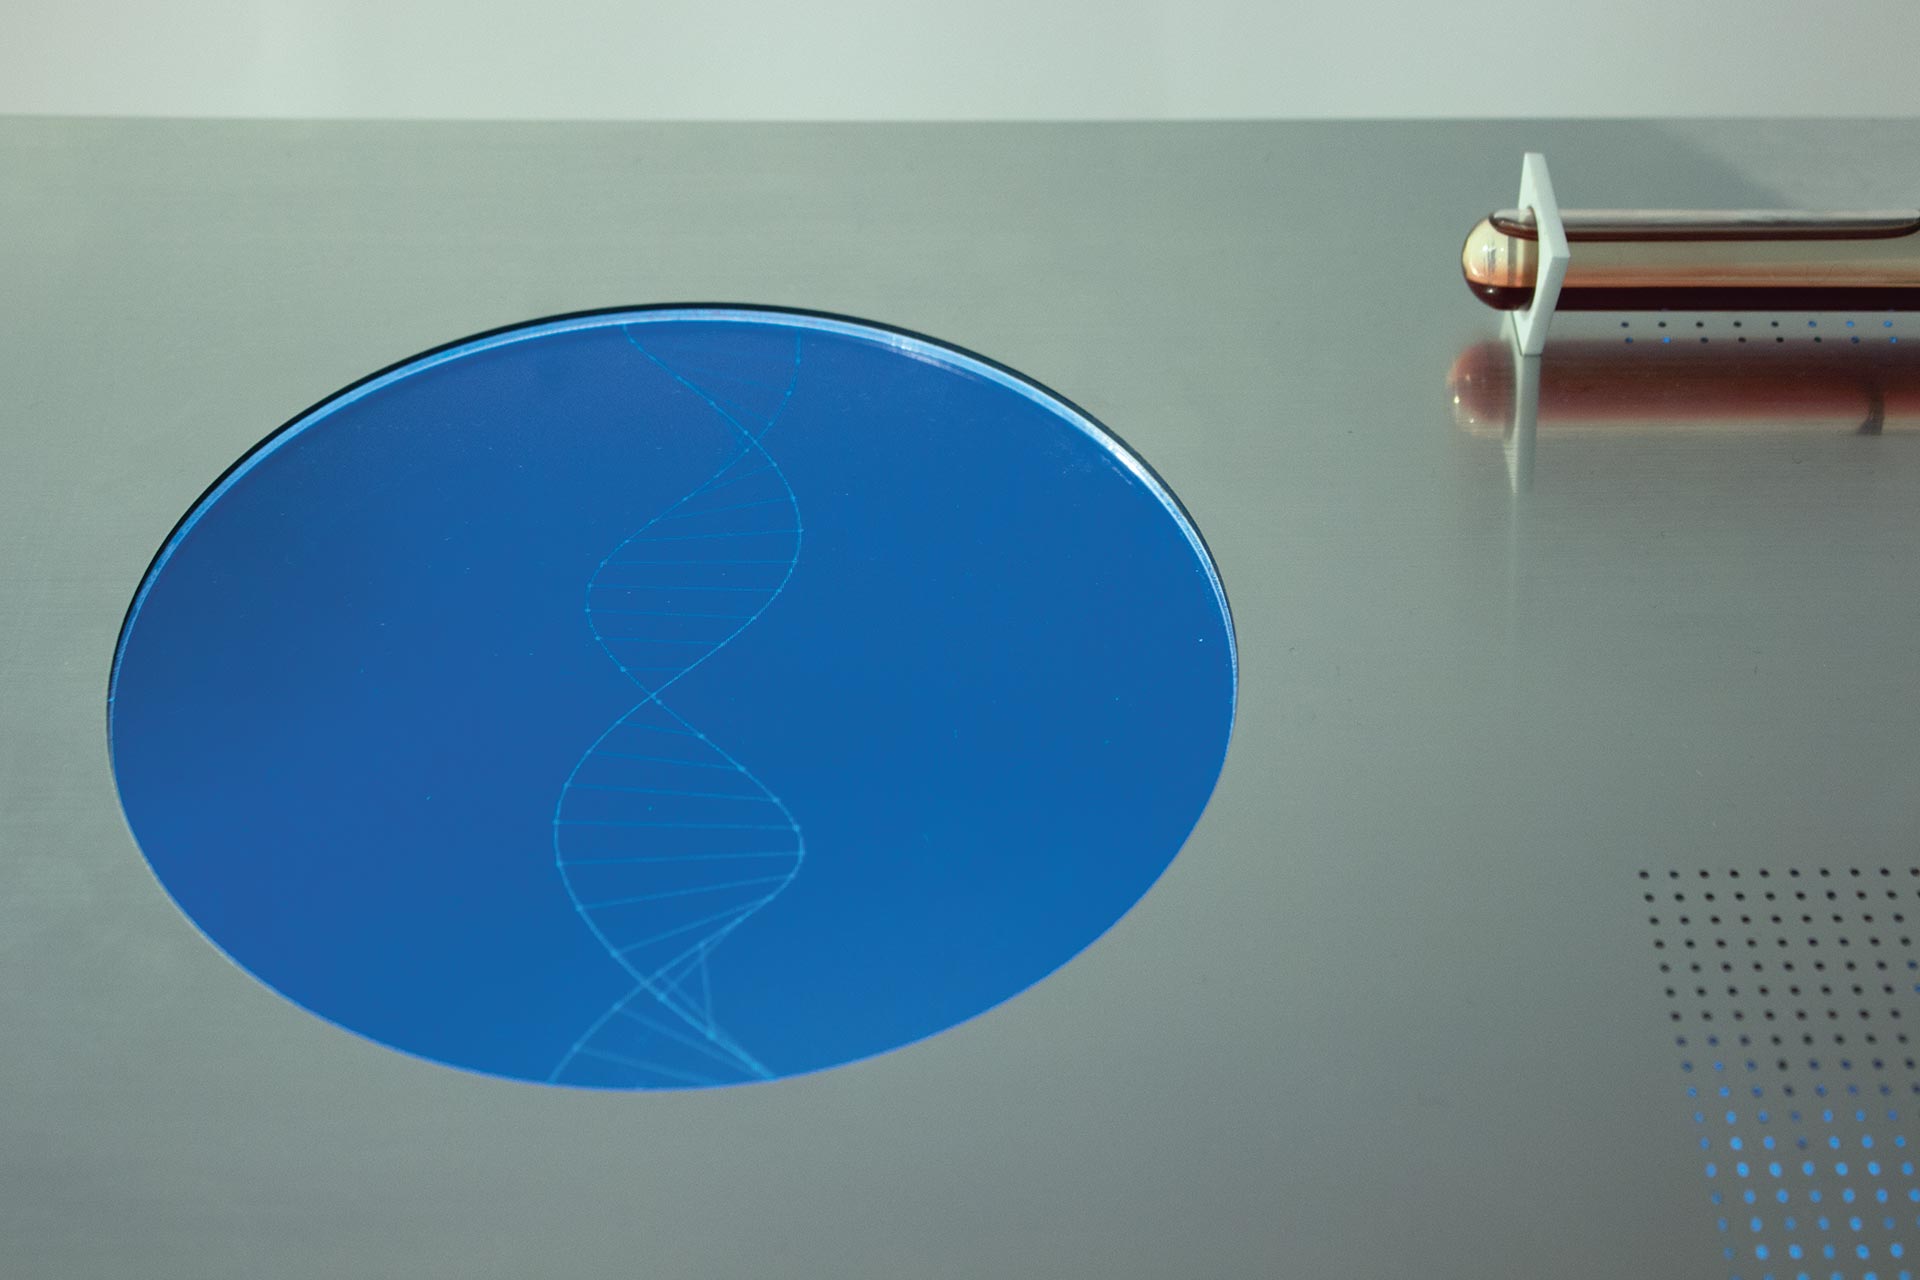

The Beauty of Oppositions

ID # 24661

Universität der Künste Berlin, DE

professors : Joachim Sauter, Jussi Angeslevä, Siegfried Zielinski

Stephan Sunder-Plassmann

contact :

www.stephansunderplassmann.com